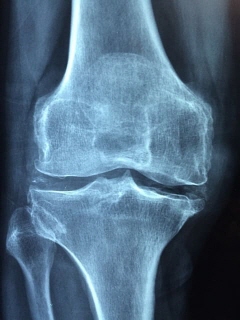

그리고 영상을 통해 염증수치 검사를 하는 방법들도 있습니다. 영상 검사에는 X-레이, CT 스캔 및 MRI 스캔과 같은 영상 검사를 사용하여 관절이나 장기와 같은 신체의 특정 부분에서 염증을 식별할 수 있습니다. 또한 고주파 음파를 사용하여 내부 장기 및 조직의 이미지를 생성하여 확인하고 관절, 힘줄 및 기타 연조직의 염증을 식별하는 데 사용할 수 있는 초음파 검사가 있습니다.